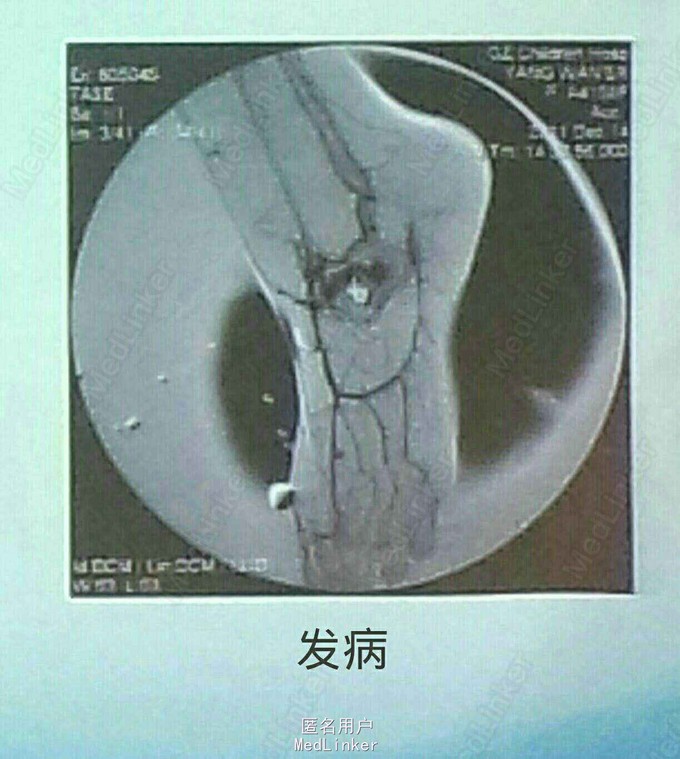

患儿女,2岁余。因足部疼痛半年余入院。伴跛行,无发热、抽搐等不适。

查体:跛行,左侧足部有压痛,局部皮温增高,双侧足背动脉不对称。心肺听诊无异常。足部听诊可闻及杂音。 辅查:血常规示血小板偏低。CTA示足部动静脉畸形。造影明确。

诊断:足部动静脉畸形 治疗:介入下造影,明确后于畸形处注射外科胶。再次造影动静脉畸形处未见造影剂。